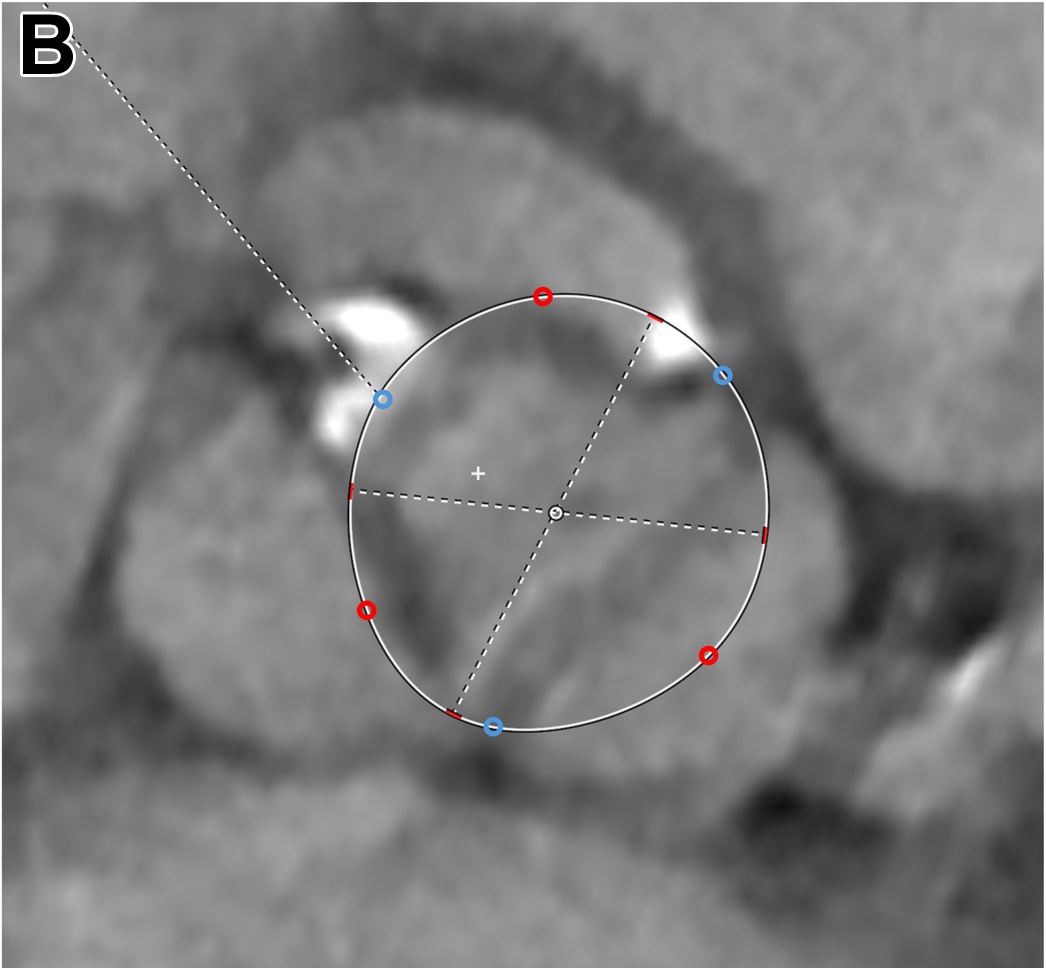

二叶主动脉瓣伴两个主动脉窦。蓝色圆点表示置于两个交界的初始定位点。红色圆点表示置于瓣叶游离缘的点,这些点向外调整至合适的半径位置。

针对不同的主动脉瓣形态,测量时的定位细节有所区别:对于三叶瓣以及具有三个主动脉窦的二叶瓣,首先在影像上标定3个瓣叶交界点,然后在每个瓣叶的游离缘处各添加1个次要标记点;对于只有两个主动脉窦的二叶瓣,则先标定2个交界点,再在两瓣叶的中点各添加1个次要点。根据瓣叶钙化的程度,这些次要定位点可适当向瓣周缘方向调整位置,以模拟瓣膜展开时瓣叶钙化可能被挤压推移的效果,从而更真实地反映植入后瓣膜可能达到的最大扩张范围。最终,通过比较多个平面测量所得的周长,取其中最小的周长值来确定人工瓣膜的尺寸。